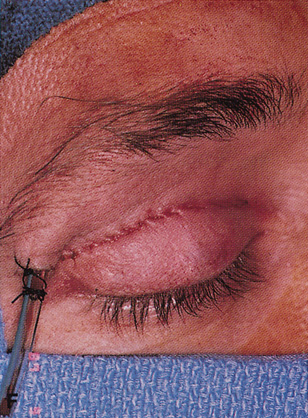

Fig. 6. Lateral orbitotomy through upper eyelid skin crease A. Photo demonstrating right globe ptosis present for more than 2 years. B. Axial CT scan showing a well outlined oval lesion in the lacrimal gland

fossa. C. Coronal CT showing lesion pushing globe inferiorly. D. Skin crease excision marked for lateral orbitotomy. E. Lateral orbital rim exposed. Bone cuts made above frontozygomatic suture

and at zygomatic arch. F. Lateral wall removed. Subperiosteal space exposed. Hard tumor could be

palpated in area of lacrimal gland. G. Benign mixed tumor of lacrimal gland removed. H. Bone sutured into place. I. Skin crease closed. |

flap from adhering to the bare bony rim. The eyelid crease

incision can be closed with a running suture (see Fig. 6I) as